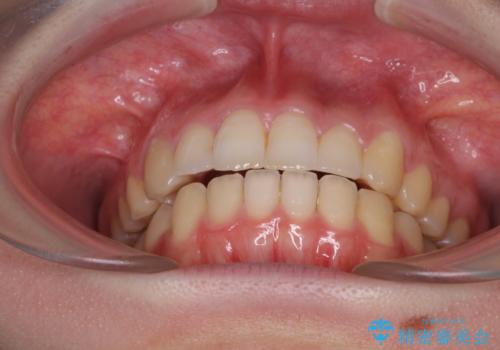

上下正中がずれていたため、抜歯による矯正治療も検討しましたが、口元がそれほど突出していなかったため、非抜歯にて矯正することになりました。

その結果正中のズレは残りましたが、口を閉じたときの感覚や奥歯の咬み合わせには全く問題なく、患者様には大変満足していただきました。